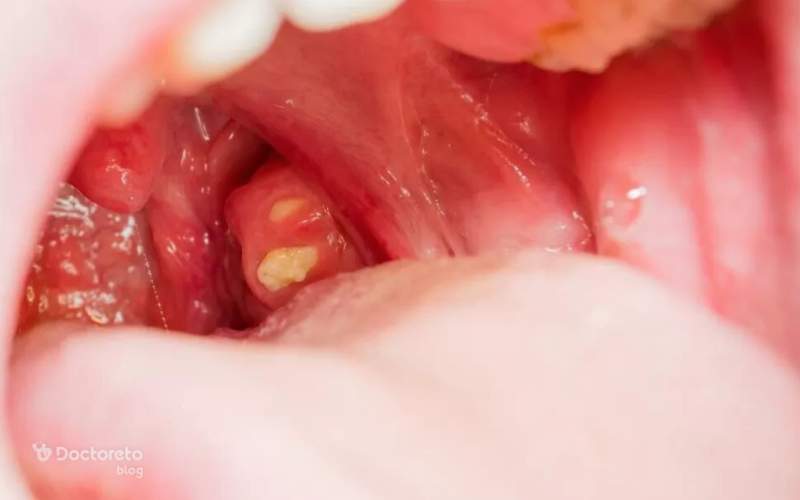

عکس تفاوت سنگ لوزه و سرطان لوزه

سنگ لوزه ظاهری کاملاً متفاوت با سرطان لوزه دارد و بسیاری از عکسهای مقایسهای این تفاوت را به خوبی نشان میدهند. سنگ لوزه معمولاً به شکل دانههای کوچک سفید یا زرد دیده میشود و روی سطح لوزه یا داخل حفرههای کوچک آن قرار میگیرد. در تصاویر، سنگ لوزه روشنتر، گردتر و قابلجابهجایی است، در حالی که سرطان لوزه به صورت زخم یا تودهای ثابت با حاشیههای نامنظم دیده میشود.

بسیاری افراد با دیدن یک نقطه سفید کوچک نگران میشوند، اما عکسها نشان میدهند که اغلب این موارد سنگ لوزه هستند، نه سرطان. این تصاویر مقایسهای برای کسانی که نگران علائم خود هستند آرامشبخش است و کمک میکند تفاوت بین سنگ و سرطان را بهتر درک کنند.